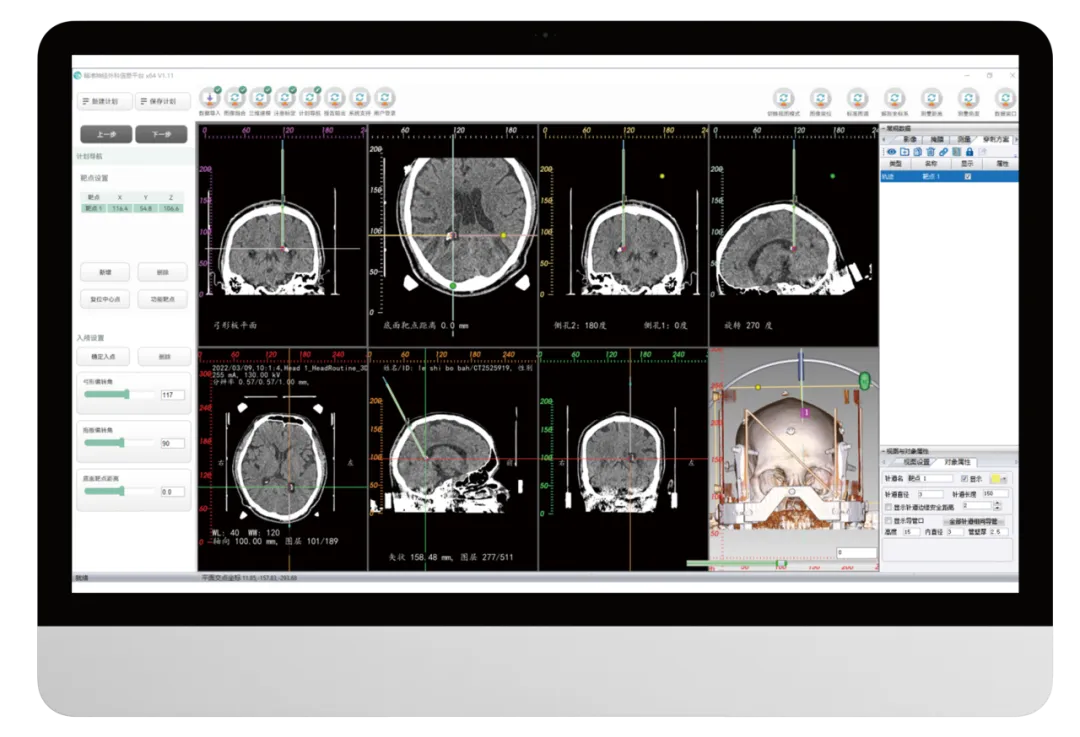

多种标定方式

可以通过传统的N/H型定位板标定,针对标定失败的情况,还可通过手动进行标定,确保百分之百能够标定成功。

手术规划

标定完成之后,进行手术路径设计,并且可以拖动路径,进行任意角度调整。